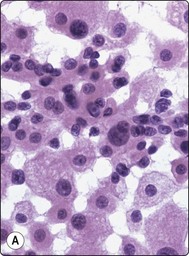

Extra-adrenal paraganglioma (Fig. 12.40)133,134

Extra-adrenal paraganglioma of the sympathetic system of the retroperitoneum down to the pelvic floor is a rare tumor. It is often functional and often malignant. Paragangliomas of the parasympathetic system of the head and neck with a similar cytomorphology are described in Chapter 4. A case of malignant metastasizing paraganglioma of the retroperitoneum is illustrated in Figure 12.40. Intranuclear inclusions are sometimes a feature of this tumor.133

image

Fig. 12.40 Paraganglioma; malignant, comparison with thyroid carcinoma

(A) Paraganglioma; loose cluster of cells with microfollicular groupings; small round dark relatively uniform nuclei; indistinct cytoplasm; fine cytoplasmic granulation not evident on photograph; (B) Metastasis of thyroid follicular carcinoma to retroperitoneal lymph node (MGG, HP); (C) Tissue section from the same case as in (A) (H&E, IP).

A 40-year-old man presented with a large palpable retroperitoneal mass. CT-guided FNB was done as one of the initial investigations and smears showed moderate numbers of cells, single and in loose acinar/follicular clusters resembling thyroid follicular epithelial cells. Nuclei were uniformly round and relatively small and showed moderate anisokaryosis. The nuclear chromatin was granular and evenly distributed; nucleoli were indistinct. The cytoplasm was pale, without distinct cell borders. Many cells showed a fine red cytoplasmic granularity (MGG). The overall pattern suggested a neuroendocrine tumor (Fig. 12.40A). The differential diagnosis included paraganglioma as well as other neuroendocrine tumors such as carcinoid and pheochromocytoma, but also metastasis of follicular thyroid carcinoma and of low-grade renal cell carcinoma. Surgical biopsy confirmed the diagnosis of paraganglioma. Serum catecholamines were not significantly raised, but abundant neurosecretory granules were demonstrated by EM. There were widespread metastases, and the patient died 4 months later.

The striking similarity between the cytology of thyroid carcinoma and that of paraganglioma is illustrated by an FNB smear of a para-aortic lymph node metastasis in a case of follicular carcinoma of the thyroid (Fig. 12.40B). The distinction between paraganglioma and medullary or follicular carcinoma of the thyroid, whether in a primary site in the neck or metastatic to other sites, requires immune marker studies.